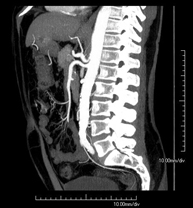

- Angio-TC aorta abdominal  Prueba diagnóstica no invasiva que consiste en el estudio de la arteria aorta abdominal obteniendo imágenes de alta definición anatómica mediante el empleo de un equipo de TC (Tomografía Computarizada) y de contraste yodado. La calidad de las imágenes permite realizar reconstrucciones en 2D y 3D gracias a estaciones de trabajo especializadas en el estudio arterial. Está indicado en aquellos pacientes con enfermedad vascular (aterosclerosis), en aneurismas de aorta, en pacientes con dolor abdominal de posible origen vascular, en estudios pre-quirúrgicos de lesiones adyacentes a la aorta abdominal como "mapa" vascular, etc. La información obtenida de forma no invasiva es indispensable para los pacientes que requieren tratamiento percutáneo o quirúrgico. En aquellos pacientes que solo requieren un seguimiento de las lesiones vasculares, esta técnica es la técnica no invasiva de elección junto con la angio-RM. Prueba diagnóstica no invasiva que consiste en el estudio de la arteria aorta abdominal obteniendo imágenes de alta definición anatómica mediante el empleo de un equipo de TC (Tomografía Computarizada) y de contraste yodado. La calidad de las imágenes permite realizar reconstrucciones en 2D y 3D gracias a estaciones de trabajo especializadas en el estudio arterial. Está indicado en aquellos pacientes con enfermedad vascular (aterosclerosis), en aneurismas de aorta, en pacientes con dolor abdominal de posible origen vascular, en estudios pre-quirúrgicos de lesiones adyacentes a la aorta abdominal como "mapa" vascular, etc. La información obtenida de forma no invasiva es indispensable para los pacientes que requieren tratamiento percutáneo o quirúrgico. En aquellos pacientes que solo requieren un seguimiento de las lesiones vasculares, esta técnica es la técnica no invasiva de elección junto con la angio-RM.

- Angio TC d'aorta abdominal Prova diagnòstica no invasiva que consisteix en l'estudi de l'artèria aorta abdominal amb l'obtenció d'imatges d'alta definició anatòmica mitjançant l'ús d'un equip de TC (Tomografia Computaritzada) i contrast iodat. La qualitat de les imatges permet realitzar reconstruccions en 2D i 3D gràcies a estacions de treball especialitzades en l'estudi arterial. Està indicat en aquells pacients que pateixen malaltia vascular (arteriosclerosi), aneurismes d'aorta, en pacient amb dolor abdominal d'un possible origen vascular, en estudis prequirúrgics de lesions adjacents a l'aorta abdominal com el "mapa" vascular, etc. La informació obtinguda de forma no invasiva és indispensable per als pacients que requereixen tractament percutani o quirúrgic. En aquells pacients que només requereixen un seguiment de les lesions vasculars, aquesta tècnica és la tècnica no invasiva d'elecció juntament amb l'angio RM. Prova diagnòstica no invasiva que consisteix en l'estudi de l'artèria aorta abdominal amb l'obtenció d'imatges d'alta definició anatòmica mitjançant l'ús d'un equip de TC (Tomografia Computaritzada) i contrast iodat. La qualitat de les imatges permet realitzar reconstruccions en 2D i 3D gràcies a estacions de treball especialitzades en l'estudi arterial. Està indicat en aquells pacients que pateixen malaltia vascular (arteriosclerosi), aneurismes d'aorta, en pacient amb dolor abdominal d'un possible origen vascular, en estudis prequirúrgics de lesions adjacents a l'aorta abdominal com el "mapa" vascular, etc. La informació obtinguda de forma no invasiva és indispensable per als pacients que requereixen tractament percutani o quirúrgic. En aquells pacients que només requereixen un seguiment de les lesions vasculars, aquesta tècnica és la tècnica no invasiva d'elecció juntament amb l'angio RM.